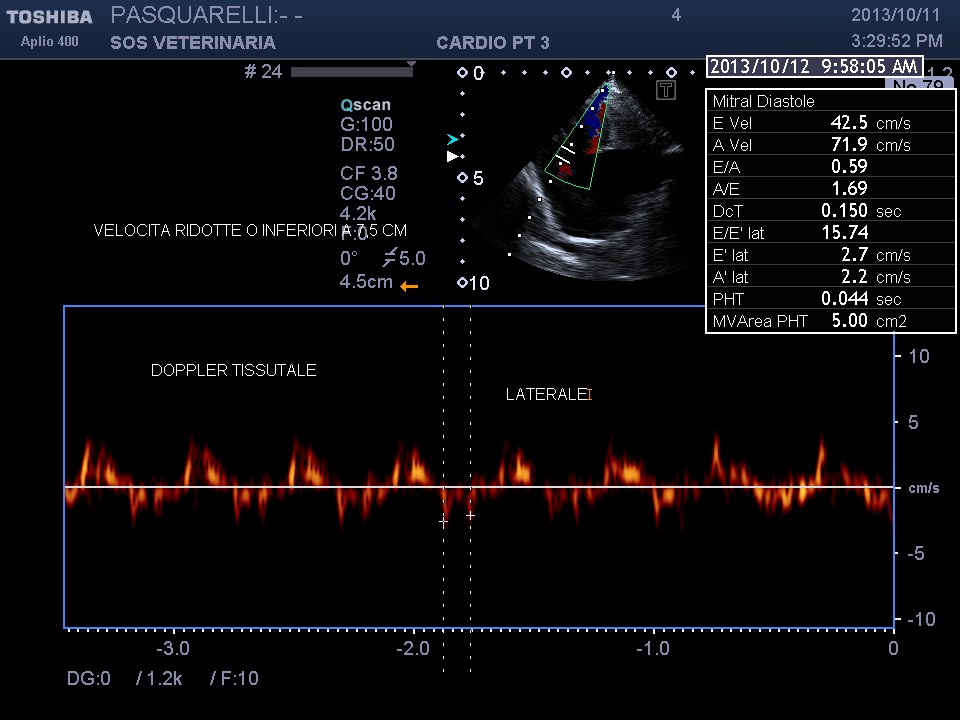

caso di cardiomiopatia ipertrofica del Maine Coone ,presentazione al pronto soccorso tipica con edema polmonare e tromboembolismo aortico completo bilaterale ,per la mia esperienza,nessun trattamento risulta essere efficace per questi soggetti, il decesso avviene nel 90%-95% dei casi e quelli che sopravvivono muoiono nelle settimane successive per le severe complicanze provocate dall’ipoperfusione ,i trattamenti trombolitici non risultano praticabili per diverse ragioni, non ultima quella economica, l’evento drammatico non e’ lo scompenso cardiaco diastolico (sul piano farmacologico gestibile) ma la trombosi aortica spesso anche polmonare .

Per avere una idea del grado di pericolosita’ della malattia basta visionare lo smoke (effetto fumo) nell’atrio sx del soggetto e il voluminoso trombo fluttuante e martellante i lembi valvolari .

Una diagnosi precoce e una corretta terapia antiaggregante avrebbe consentito a questo soggetto di vivere tranquillamente fino allo scompenso congestizio diastolico inevitabile con l’aumentare del grado di ipertrofia.